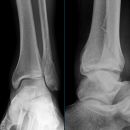

Sprunggelenk

Weber A

Weber B

Weber C + dorsales Volkmann

Trimalleoläre

Vorderes Volkmann + lat. Talusschulter